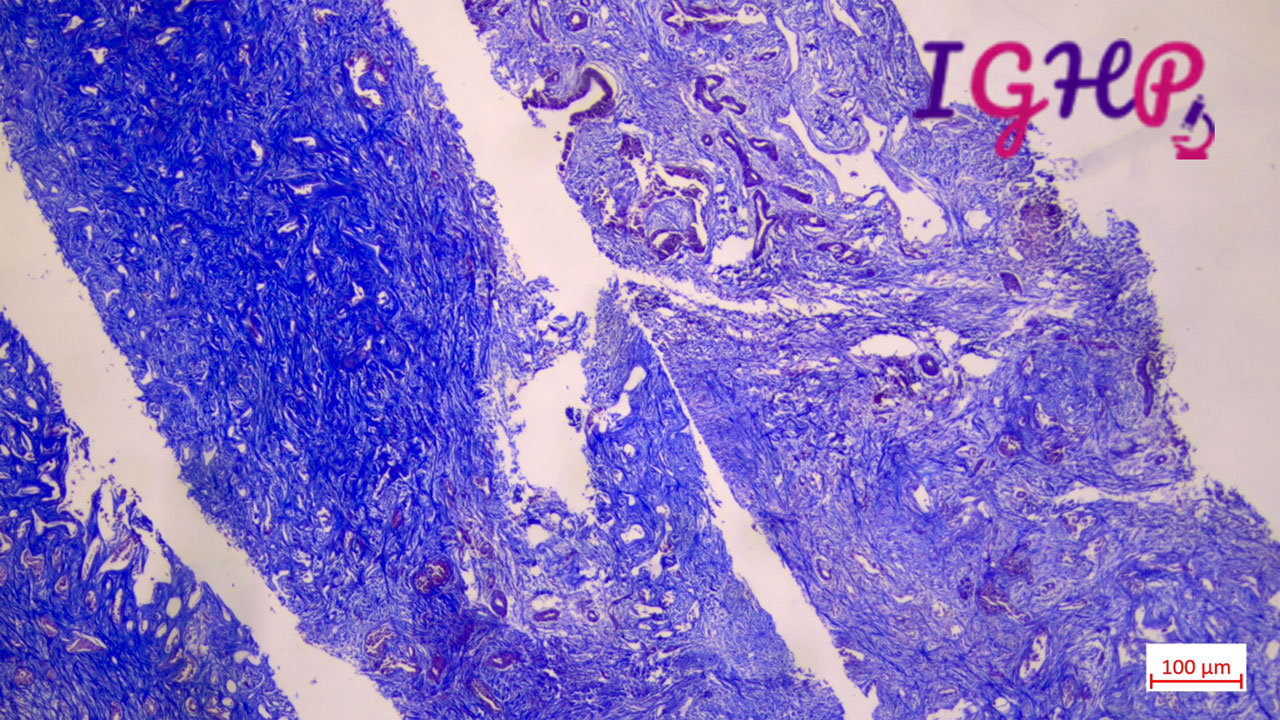

Microscopic Images-

Microscopic examination showed atypical bile ductular proliferation in dense sclerotic stroma. Areas of mild nuclear pleomorphism noted. Intraluminal apoptotic debris seen.